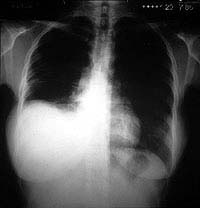

Esquema 44 Comentario placa 44 La primera impresión es que el diafragma derecho se encuentra ascendido. Sin embargo, la historia del paciente y el desplazamiento del vértice de la supuesta cúpula diafragmática hacia la pared lateral del tórax, hicieron sospechar un derrame infrapulmonar. La cúpula del diafragma alcanza su mayor altura a nivel de la linea medioclavicular. Para comprobar esta hipótesis se tomó una radiografía en decúbito lateral con rayo horizontal (placa 45). |